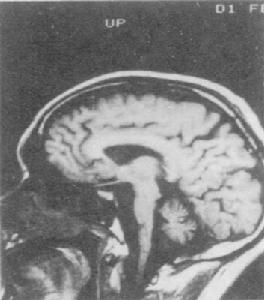

側腦室其發生機制不詳,可能與酒精對腦的直接損害及營養障礙,尤其是維生素B1的缺乏有關。多見於長期大量飲酒的男性中老年人。發病隱匿,緩慢進展。早期常有焦慮不安、頭痛、失眠、乏力等。逐漸出現智力衰退和人格改變。此外,部分病人還可合併有周圍神經病變、肌肉萎縮,甚至出現震顫、幻覺、妄想和癲癇發作等嚴重酒精中毒的表現。頭顱CT示側腦室對稱性擴大,腦溝、半球間裂和外側裂增寬等腦萎縮的表現。

大腦神經元 一次CT掃描發現腦溝加深,腦裂變寬、腦室對稱性擴大等腦萎縮的改變,並不代表腦組織不可逆的喪失。近年來通過CT或MRI研究,發現有些酗酒者所見的這種CT改變在不同程度上是可逆的。這種可逆性說明是腦內液體發生了轉移,而非腦組織喪失。這可能與戒酒後腦中水和電解質恢復正常有關。也可能與腦膠質細胞和神經元蛋白的再生有關。

4、頭顱CT示腦溝增寬、腦回變小、腦池和腦室擴大等腦萎縮的表現。